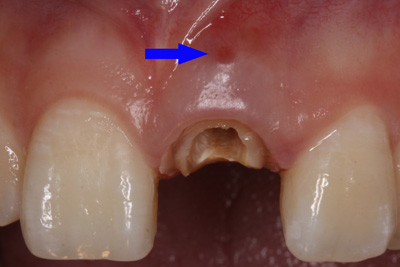

患者外院螺紋樁核加樹脂冠

X線片顯示螺紋釘出根管壁

唇側(cè)出現(xiàn)瘺管